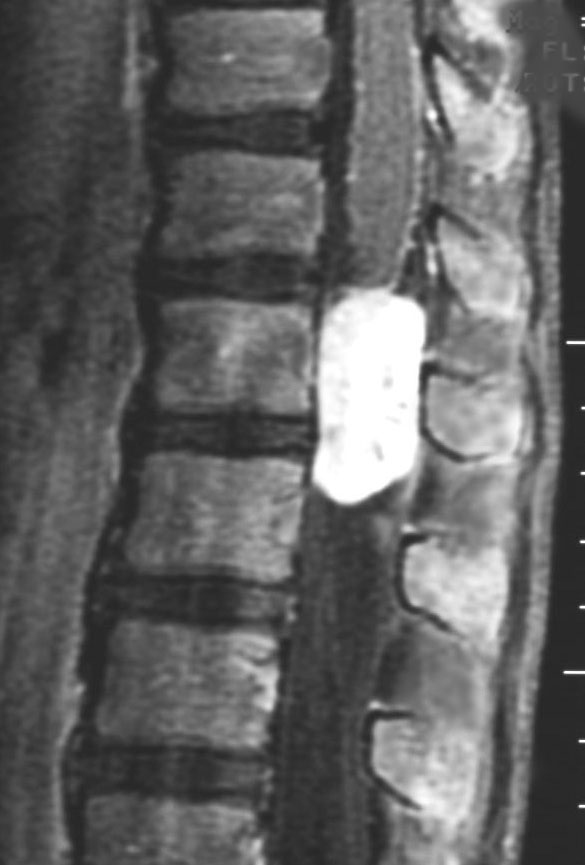

MRI診断

- MRIでは腰部脊柱管内に境界明瞭な,ガドリニウムで強く増強される腫瘍です

- 腫瘍内嚢胞が多数見られることや腫瘍内出血の所見も特徴的なものです

- 緩徐に増大するので症候性となる時には腰部脊柱管内くも膜下腔を埋め尽くすようなものもあります

脊髄円錐下端の終糸から発生した典型的な粘液乳頭状上衣腫です。おそらく手術合併症を生じることなく全摘出できるタイプです。